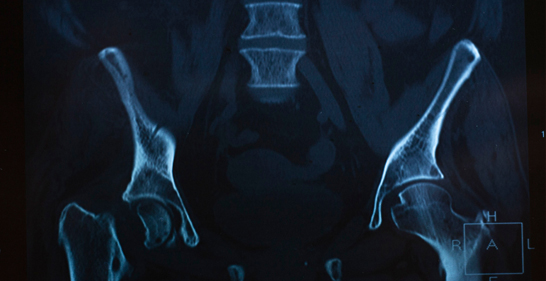

14. Pelvic Fracture

A break in any of the bones forming the pelvis.

Icon Cause: High-impact accidents, falls in older adults.

Icon Symptoms: Severe pelvic pain, difficulty standing or walking.

Icon Treatment: Bed rest, physical therapy, or surgery for severe fractures.